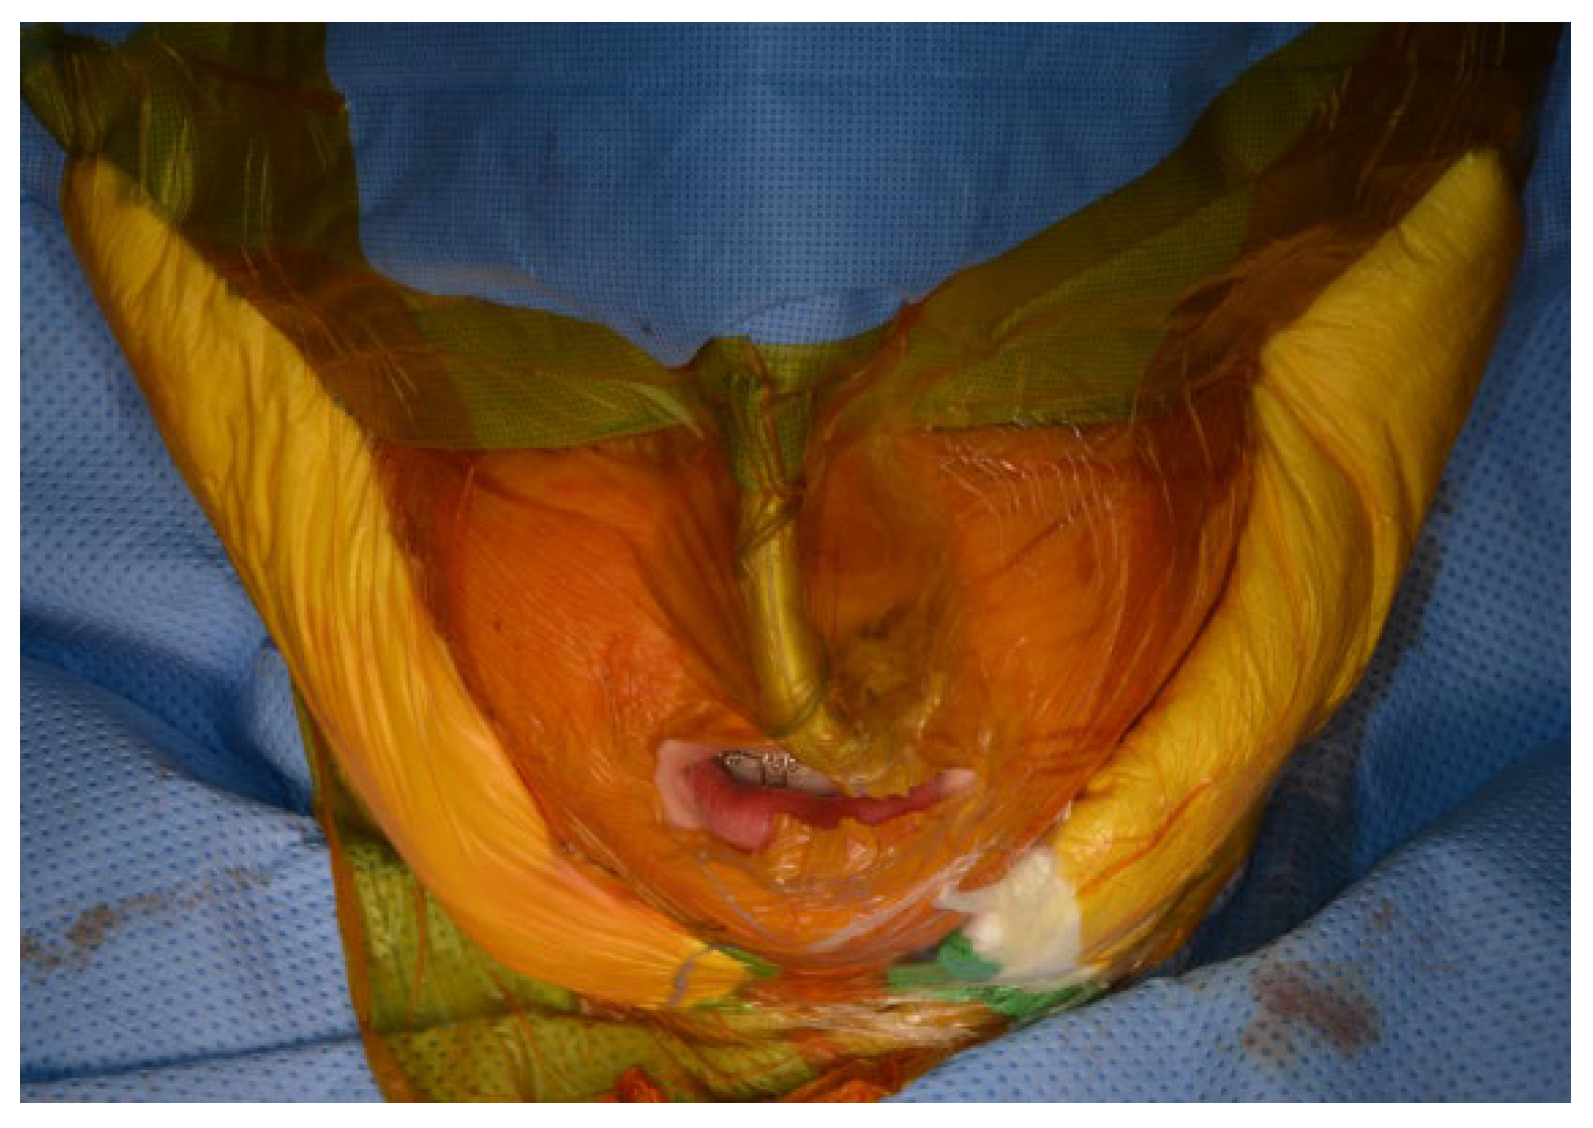

7.8. Maxillomandibular Fixation

After the mandible has been mobilized and the preparation of the TMJ area is completed, the TMJ surgical field is isolated using suitable barriers (Ioban

®, Tegaderm

®, etc.) to maintain sterility (

Figure 9). Additional surgical drapes are placed over previous ones and the exposure is limited to avoid cross-contamination (

Figure 10).

The Ioban® barrier over the mouth is carefully cut through to expose the oral cavity. In cases where significant mandibular advancement or counterclockwise rotation is planned, there is an increased risk of mucosal tear along the anterior border of the mandible. Therefore, upon accessing the oral cavity, it is crucial to thoroughly examine for any perforations. If a perforation is detected, extensive irrigation with 0.12% Chlorhexidine is performed and the perforation is meticulously closed using a watertight closure technique with 3-0 Vicryl sutures.

Next, the intermediate splint is placed, and the patient is placed into MMF. For this step, the authors recommend placement of intermaxillary fixation (IMF) screws, even if the patient has orthodontic appliances since this helps to bring the mandible to the splint and provides a more stable MMF. Since the occlusion is not typically checked after the joint is placed, we rely on a very stable and firm MMF using multiple IMF screws and 24-gauge wire.

After this is completed, the additional surgical drapes are removed and the surgeon changes gloves and gown. The oral cavity is isolated again using appropriate barriers such as Ioban®, Tegaderm® or similar materials to avoid cross-contamination.